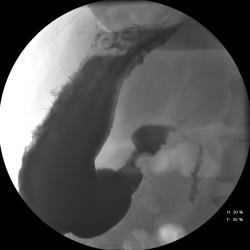

Женищина 49 лет, повышенного питания, обратилась с жалобами на потерю аппетита, жжение после чуть острой пищи, отрыжку с неприятным запахом, иногда темный стул, несколько похудела. Данные жалобы с сентебря-октября. Никуда не обращалась, коррегировала питанием. В последнее время стало хуже, обратилась...

Привратник удлиннен и ригиден, такое бывает при раке. Рек. ЭГДС.

Вы правы. я несколько недорасказал. женщина пришла уже с фгдс - инфильтративно-язвенный процесс в выходном отеде желудка у привратника по малой кривизне с переходом на переднюю стенку. так что прицельно смотрел этот отдел. перистальтка была ослаблена, краевой дефект в препилорической зоне по малой кривизне, передней стенке, кажущееся удлинение привратника, нависание основания луковицы - вообщем как в книжке. эвакуация было не изменена. написал рак выходного отдела желудка. вчера пришла гистология - высокодиф-я аденокарцинома. вот такая история.

Пока, касаясь только луковицы, но не препилорического отдела. "Ниши" в луковице есть, и они нуждаются в объяснении.

Конечно, в пилорическом канале уже растет, и "это" растет, уже и препилорической части и в луковице 12-ти перстной кишки.